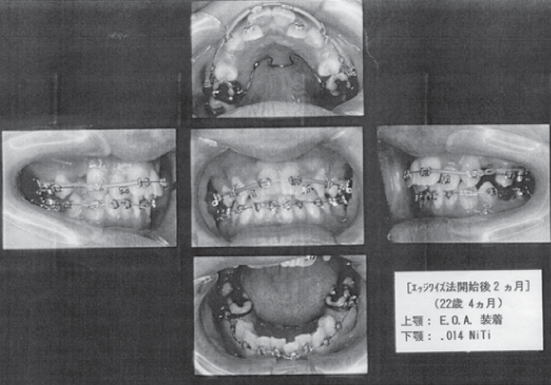

私の矯正治療について、経過写真を見ながら、少しご説明しましょう。